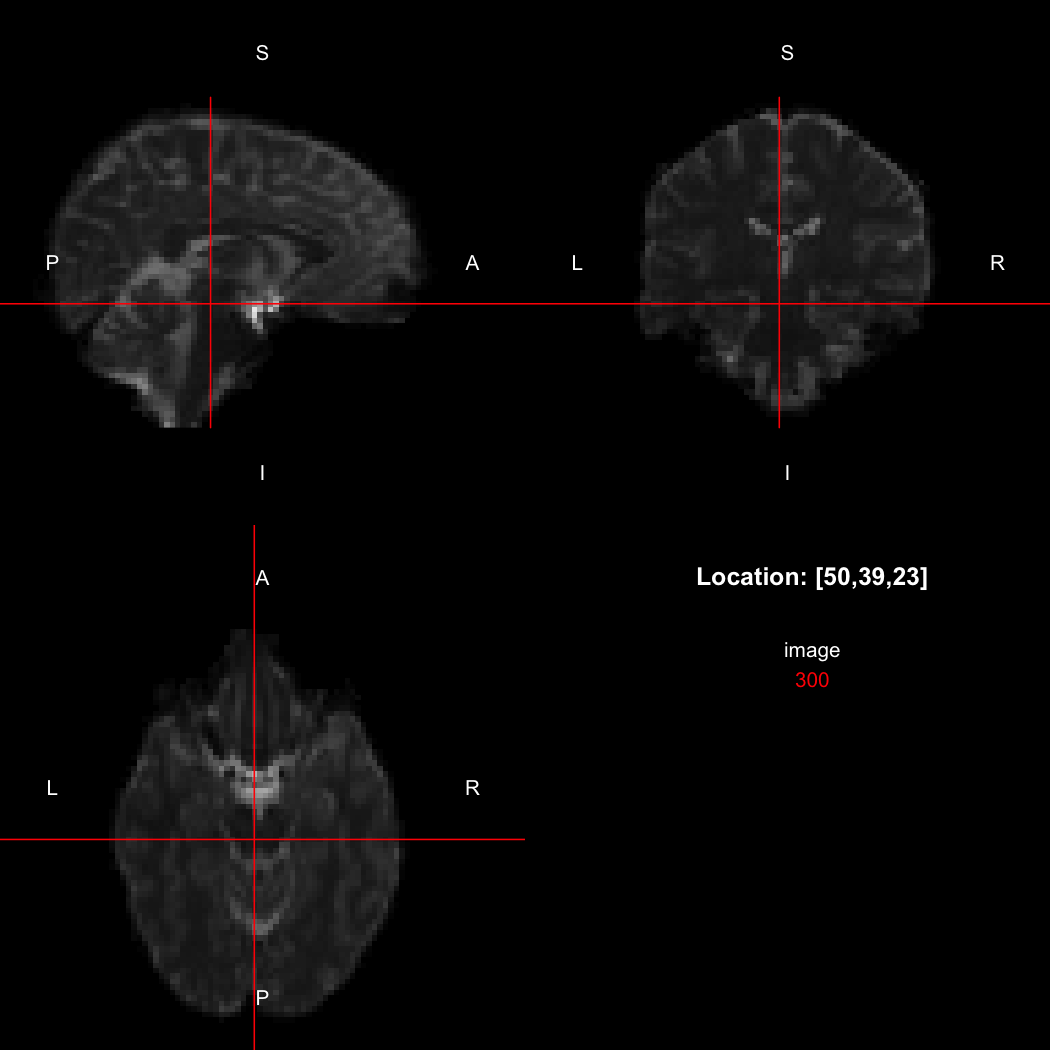

We can also use the RNifti image viewer to visualise the image.

view(image)

plot of chunk original